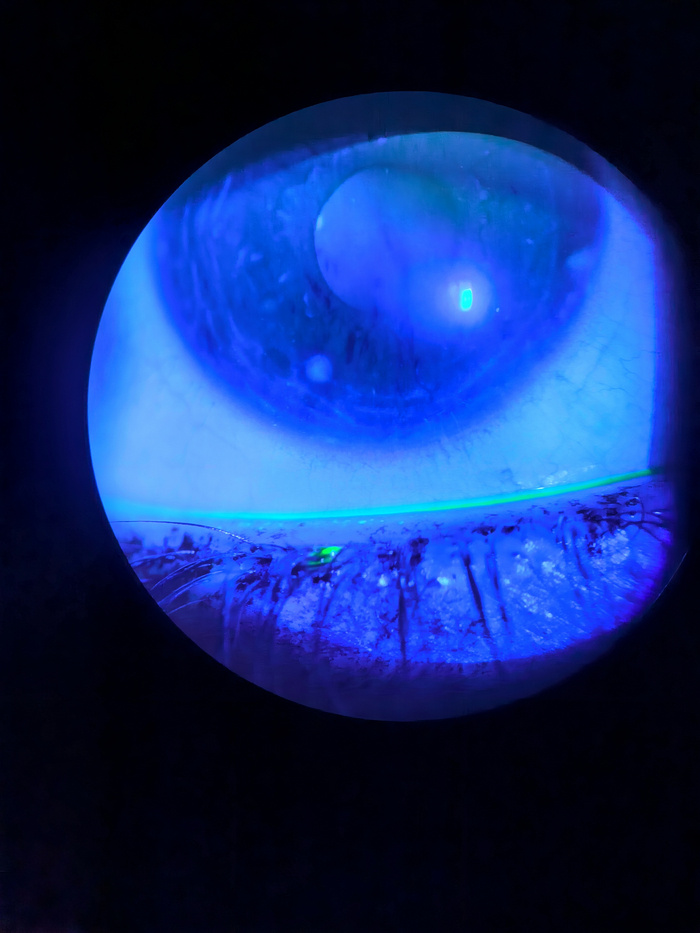

Тайский эксперимент с постакне-пятнами

Тайские дерматологи собрали 72 человека с лёгким и умеренным акне, у всех остались эритемы (красные пятна) и пигментация (коричневые пятна) — этакие памятники прошлым прыщам. Половину участников намазали гелем с 15-процентной азелаиновой кислотой, половину — плацебо. Никаких других средств — только солнцезащитный крем. Курс — 12 недель.

Исследование было рандомизированным (распределение по группам — случайное), двойным слепым (ни пациенты, ни врачи не знали, кто получает настоящий препарат), плацебо-контролируемым (есть контрольная группа для сравнения). То есть по всем канонам доказательной медицины.

Замеры делали серьёзные: дерматоскоп, система VISIA (специальная камера с разными спектрами света, которая выявляет скрытую пигментацию), индекс PAHPI (числовая оценка тяжести пятен: размер, интенсивность, количество), Mexameter (уровень меланина и гемоглобина в коже), корнеометр (влажность рогового слоя), тевометр (трансэпидермальная потеря воды, то есть насколько хорошо кожа держит влагу, цел ли барьер), себуметр (уровень жирности кожи).

<a href="https://pmc.ncbi.nlm.nih.gov/articles/PMC11116308/" target="_blank" rel="nofollow noopener">Оценка следов от акне с помощью анализатора кожи VISIA и дерматоскопии</a>

Оценка следов от акне с помощью анализатора кожи VISIA и дерматоскопии

К концу 12-й недели кожа в группе азелаиновой кислоты вздохнула с облегчением. Эритемы стали заметно бледнее и меньше по площади, общий индекс PAHPI упал почти вдвое. Пигментация тоже сдала позиции: интенсивность цвета упала наполовину, размер и количество коричневых пятен уменьшились, уровень меланина в коже снизился, пятна заметно посветлели.

При этом физиология кожи не пострадала, а даже улучшилась. Влажность рогового слоя повысилась примерно на четверть. Трансэпидермальная потеря воды осталась стабильной — барьер остался целым. Жирность кожи снизилась, а это значит меньше питания для бактерий, меньше риска новых воспалений.

Качество жизни участников выросло: индекс DLQI упал с умеренного влияния (когда пятна реально мешают) до минимального (когда они почти не беспокоят). В группе плацебо изменения были минимальными или вообще отсутствовали.